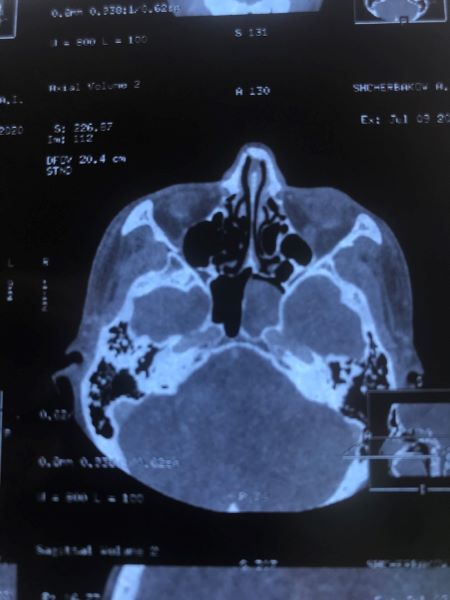

Киста основной пазухи

Пациент обратился в клинику №1 ВиТерра Беляево к ЛОР-врачу Богдановой Е.С. с жалобами на выраженную головную боль в течение 2-х лет! Неоднократно обследован и проходил лечение в других клиниках. Без эффекта.

Пациент после осмотра был направлен доктором Богдановой Е.С. на КТ придаточных пазух носа в клинике ВиТерра. По результатам обследования обнаружена киста основной пазухи слева. Пациент направлен в стационар для хирургического лечения.

Через 2 месяца пациент пришёл на контрольный осмотр.

Жалоб не предъявляет. Головные боли купировались сразу же после операции.